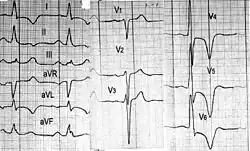

- Электрокардиография — никогда не бывает нормальной и поэтому является удобным методом скрининга. Обнаруживают признаки увеличения левого желудочка и левого предсердия. Возможны также признаки увеличения правого желудочка. Особенно характерны глубокие отрицательные зубцы Т различных локализаций, глубокие зубцы Q (часто в области перегородки). Выявляют различные нарушения ритма и проводимости.

- Мониторирование ЭКГ — выявляет нарушения ритма, что важно для прогноза и оценки возможности развития внезапной смерти.